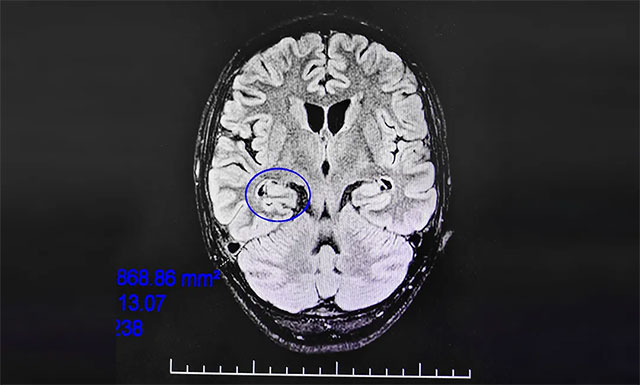

▲ 通过系列检查最终明确患者致癫灶

脑电监测崔丽华主任根据脑电图监测分析指出,患者双侧有癫痫波,右侧较为严重。磁共振检查,患者右侧颞叶、海马结构代谢异常。既往史显示,患者1岁时有头部压伤及缺氧窒息病史。

该患者经系统内科药物治疗不佳,确诊为药物难治性癫痫,经过系列检查最终明确患者致癫灶位于右侧颞叶、右侧海马。手术指征明确,未见明显手术禁忌症。